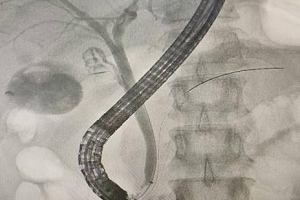

一位心梗患者的5小时生死救援与16天生命守护

“医生,我胸口像压了块大石头!”,51岁的李先生因突发剧烈胸痛,被紧急送入玉溪市人民医院心内科CCU,入院时患者大汗淋漓、血压下降,四肢发凉,心电图提示急性广泛前壁心肌梗死,一场与时间赛跑、与死神竞速的生死救援就此展开。